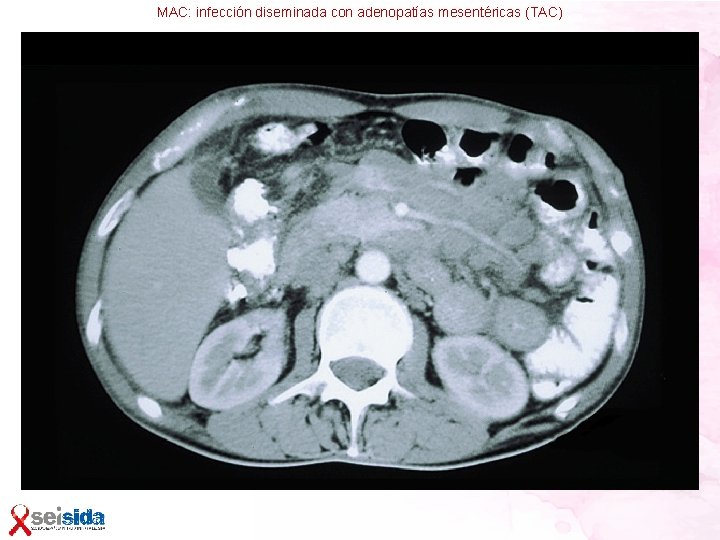

Micobacterias atípicas • Poco frecuentes en nuestro medio • Más frecuentes en varones y drogadictos • El 89% de los casos tienen <50 CD 4 Especies patógenas: • Micobacterium avium intracelullare 73%. También llamado Complejo MAI o MAC • Micobacterium xenopi 21% • Micobacterium kansasii 6% Patogenia • El complejo MAI se encuentra en las heces de los pájaros, de donde puede pasar al suelo y al agua potable • A pesar de estos hallazgos, no está claro cuál es la fuente de infección • Tampoco se conoce con claridad si la infección que produce enfermedad es una infección reciente o es una reactivación de un reservorio endógeno

Micobacterias atípicas-Clínica LINFADENITIS • Aumento localizado o generalizado de adenopatías con o sin fiebre • Granulomas típicos en biopsia sólo en 1/3 • Bacilos ácido-alcohol resistentes (BAAR) en ganglio: – >100 CD 4, pensar en Tuberculosis – <100 CD 4, pensar en tuberculosis y MAC INFECCIÓN PULMONAR • Síntomas leves: tos, expectoración, disnea, fiebre, sudoración • RX de tórax: – – – Infiltrado intersticial o retículo-nodular 50% Infiltrado alveolar 20% Afectación sólo de lóbulos superiores <10% Adenopatías hiliares <15% Cavitación <5% Derrame pleural: raro

Micobacterias atípicas-Clínica GASTROINTESTINAL • Diarrea, dolor abdominal, signos de malabsorción, pérdida de peso • Adenopatías retroperitoneales • Úlceras en la mucosa intestinal INFECCIÓN DISEMINADA • Fiebre, escalofríos, sudoración • Debilidad • Náuseas, vómitos, diarrea, dolor abdominal • Pérdida de peso • Hepatoesplenomegalia • Linfadenopatía • Anemia, trombopenia, aumento de fosfatasa alcalina • Hemocultivos + en 86 -98% • Puede aislarse en casi todos los órganos

Micobacterias atípicas Diagnóstico • Aislamiento e identificación en cultivo de un sitio estéril: sangre, hígado, médula ósea, LCR • Siempre hay que descartar que se trate de una contaminación de laboratorio • Aislamiento en esputo, broncoaspirado, heces, descartar que se trate de una colonización (la micobacteria no está produciendo síntomas) y buscarlas en otros órganos (sangre, médula ósea…) • PACIENTE VIH+ CON AFECTACIÓN PULMONAR Y MAC EN 3 Ó MÁS MUESTRAS (ESPUTO, BRONCOASPIRADO, LAVADO BRONCOALVEOLAR), SIN OTRA CAUSA APARENTE, INICIAR TRATAMIENTO ANTI-MAC

Micobacterias atípicas Tratamiento • Claritromicina 500 mg/12 h ó Azitromicina 600 mg/día + • Otro antimicobacteriano: – – Etambutol 600 -1000 mg/ 12 h Ciprofloxacino Rifampicina, Rifabutina Amikacina • Puede ser útil la asociación de 3 fármacos (para MAC Claritromicina + Etambutol + Rifabutina) • Tratamiento de por vida, recaídas si abandono, aunque se puede plantear la retirada tras 12 meses si CD 4 >100 Profilaxis • No indicada en España por la baja prevalencia

MAC: infección diseminada con adenopatías mesentéricas (TAC)